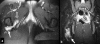

Introduction: Quadratus femoris tear is an uncommon injury, which is only rarely reported in the literature. In the majority of cases the correct diagnosis is delayed due to non-specific symptoms and signs. A magnetic resonance imaging scan is crucial in the differential diagnosis since injuries to contiguous soft tissues may present with similar symptoms. Presentation with sciatica is not reported in the few cases existing in the English literature and the reported treatment has always been conservative.

Case presentation: We report here on a case of quadratus femoris tear in a 22-year-old Greek woman who presented with persistent sciatica. She was unresponsive to conservative measures and so was treated with surgical decompression.